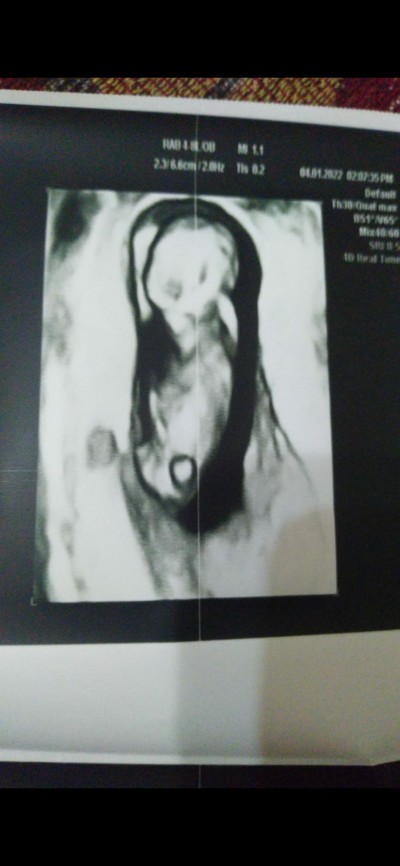

Kizlar bu arkadaşımın hayırlısı ne ise o olsun tabiki ama kocasi tarafindan baya baski var cahillik olsa gerek erkrk cocuk deyip duruyorlar kiza yazik oda her zaman hayirlisini isteyen biri buraya atmak istedim bende belki anlayan falan filan olur belki diye